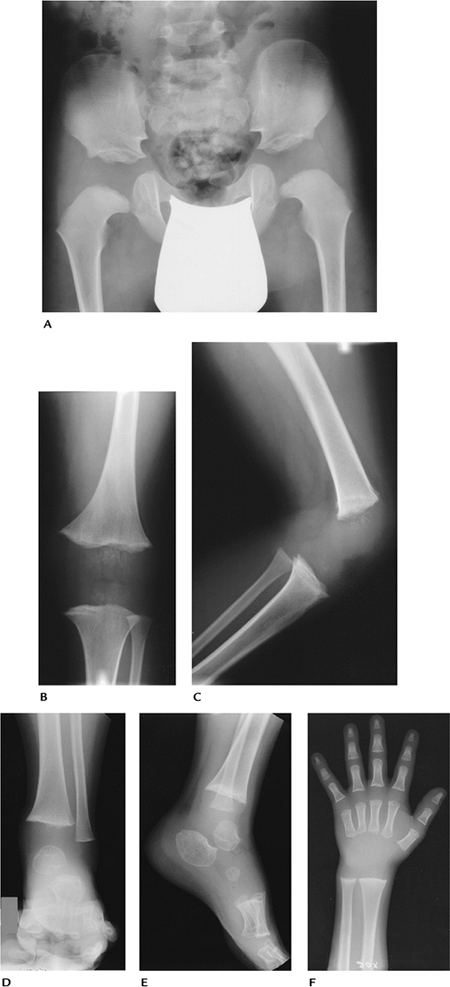

FIGURE 15-19 Hereditary multiple exostosis. Radiographs of the humeri (A,B), left hand and wrist (C), both ankles (D), and feet (E) demonstrate multiple exostoses with bone and joint deformities most obvious in the hand and wrist.